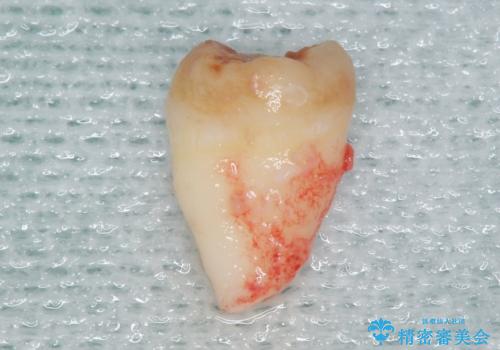

使っていない親知らず(左上8)を左上7抜歯窩に移植し、支台歯としてブリッジによる補綴治療を行いました。